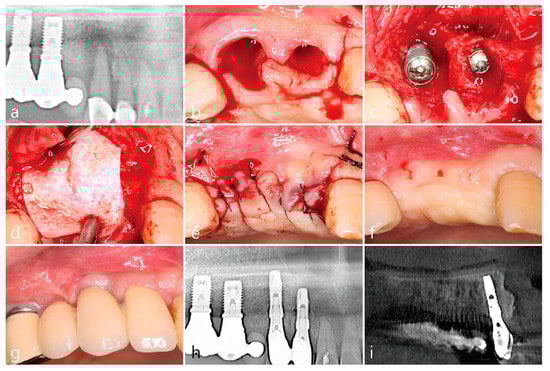

4. Case 2

- A tooth or implant with severe bone loss was removed using extraction forceps under local anesthesia with 2% lidocaine containing 1:100,000 epinephrine;

- A midcrestal incision and two buccal vertical incisions were made. Before raising the flap, special care was taken to ensure a clean dissection of the IGT from the underlying flap without any damage and the IGT is still well-attached to the flap. The IGT was then further separated from the bony housing by using a curette with various curvatures and a periosteal elevator.

- The IGT attached to the buccal flap was dissected to an appropriate thickness using a #15 blade so that the base of the IGT was still attached to the existing flap, and the flap was eventually extended. Periosteal releasing incisions were not performed at the flap base.

- The extraction socket was thoroughly debrided using a Molt curette and a titanium brush.

- A surgical guided stent was used so that the implant (Implantium, Dentium, Suwon, Korea) was placed 2.0 mm subcrestal to the level of the adjacent bone in the extraction socket.

- A synthetic osteoconductive bone graft substitute composed of hydroxyapatite (HA) and beta-Tricalcium phosphate (β-TCP) (Osteon III, Genoss, Suwon, Korea) and a resorbable collagen membrane (Genoss, Suwon, Korea) were placed to cover the implant and the peri-implant osseous defect.

- After covering the bone graft with the collagen membrane, the extended IGT was sutured with the palatal flap with 4-0 Catgut. Next, the buccal flap was closed using 4-0 nylon or black silk.

- Uncovering procedures were performed 4–6 months after initial surgery. Under local anesthesia, the buccal flap was reflected, the regenerated tissue above the implant cover screw was removed, and the healing abutment was connected to the implant. The buccal flap was closed using 4-0 Catgut or black silk. Antibiotics and anti-inflammatory drugs were prescribed for 5 days. The prosthesis was installed 2 months after uncovering.